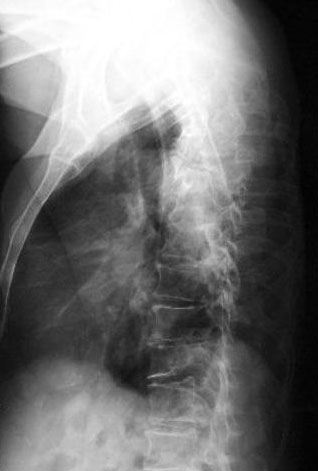

Osteoporosis. Cifosis.

Escoliosis, artrosis, aplastamiento...